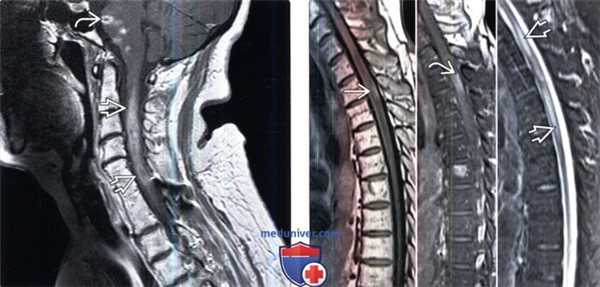

(Слева) Сагиттальный срез, Т2-ВИ: признаки диффузного отека спинного мозга от уровня цервикомедуллярного перехода до С5. Фокус низкой интенсивности сигнала на уровне С2-С3 представляет собой метастаз карциномы легкого.

(Справа) Сагиттальный срез, FS T1-ВИ с КУ: накапливающий контраст интрамедуллярный очаг на уровне С3, представляющий собой метастаз почечноклеточной карциномы. Объемный эффект опухоли вкупе с отеком приводит к веретеновидному утолщению спинного мозга.

(Слева) Сагиттальный срез, STIR МР-И, пациент с метастазами мелкоклеточного рака легкого: признаки отека дистальной части грудного отдела спинного мозга в виде зоны высокой интенсивности сигнала.

(Справа) Сагиттальный срез, Т1-ВИ с КУ: фокус накопления контраста в дистальной части грудного отдела спинного мозга, представляющий собой метастаз мелкоклеточного рака легкого.

(Слева) Сагиттальный срез, Т1-ВИ с КУ: признаки распространения опухоли головного мозга (глиомы) из ствола мозга в шейный отдел спинного мозга. В стволе мозга видны множественные фокусы патологического накопления контраста. Спинальные метастазы мультиформной глиобластомы встречаются очень редко, диссеминация этой опухоли обычно наблюдается на поздней стадии заболевания.

(Справа) Сагиттальные МР-И: интрамедуллярное очаговое поражение спинного мозга. В Т1 -режиме очаг отличается гиперинтенсивным сигналом. В FS Т1-ВИ с КУ-это накапливающий контраст очаг с нечеткими границами, который в ходе дальнейшего обследования оказался метастазом меланомы. В Т2-режиме видны признаки распространенного отека спинного мозга.